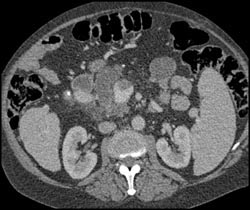

Stretching of Arterial Vessels Due to Hepatic Congestion